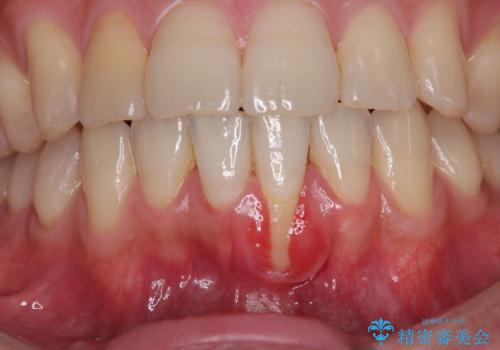

一度の処置で十分に根面被覆ができました。

舌側に歯石が溜まりやすく、やや出血が認められるため、定期的なクリーニングが大切となってきます。